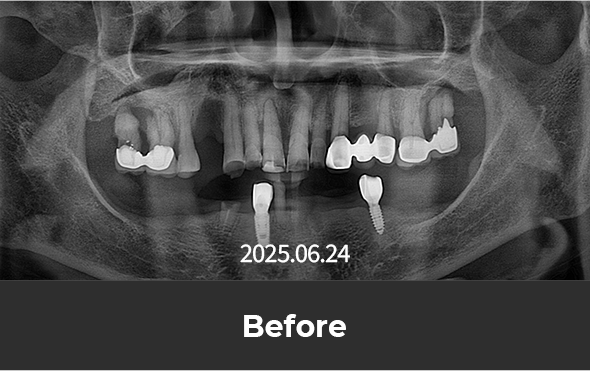

잇몸뼈가 많이 소실된 경우에도

각도 식립 등의 방법을 통해 시술이 가능합니다.

치료 후 사진

[ 환자분의 동의서 작성 후 게시하였습니다 ]